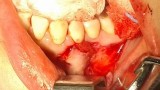

Bogata w płytki i leukocyty fibryna jest stosowana w regeneracji tkanek od ponad 15 lat. Pozytywny wpływ PRF (platelet-rich fibrin) na regenerację tkanek miękkich jest niewątpliwy, bezsporny i częściowo udowodniony w badaniach klinicznych i analizach biochemicznych. Wpływ PRF na regenerację tkanki kostnej jest obserwowany klinicznie, ale nadal niedostatecznie poznany jest mechanizm tego zjawiska.

Platelet- and leukocyte-rich-fibrin has been used in regeneration of tissue for more than 15 years. The positive influence of PRF on the regeneration of soft tissue is undoubtedly, without question and partially proven in clinical studies and biochemical analysis. Influence of PRF on regeneration of bone tissue is observed clinically but the mechanism of this phenomenon is still not sufficiently known.